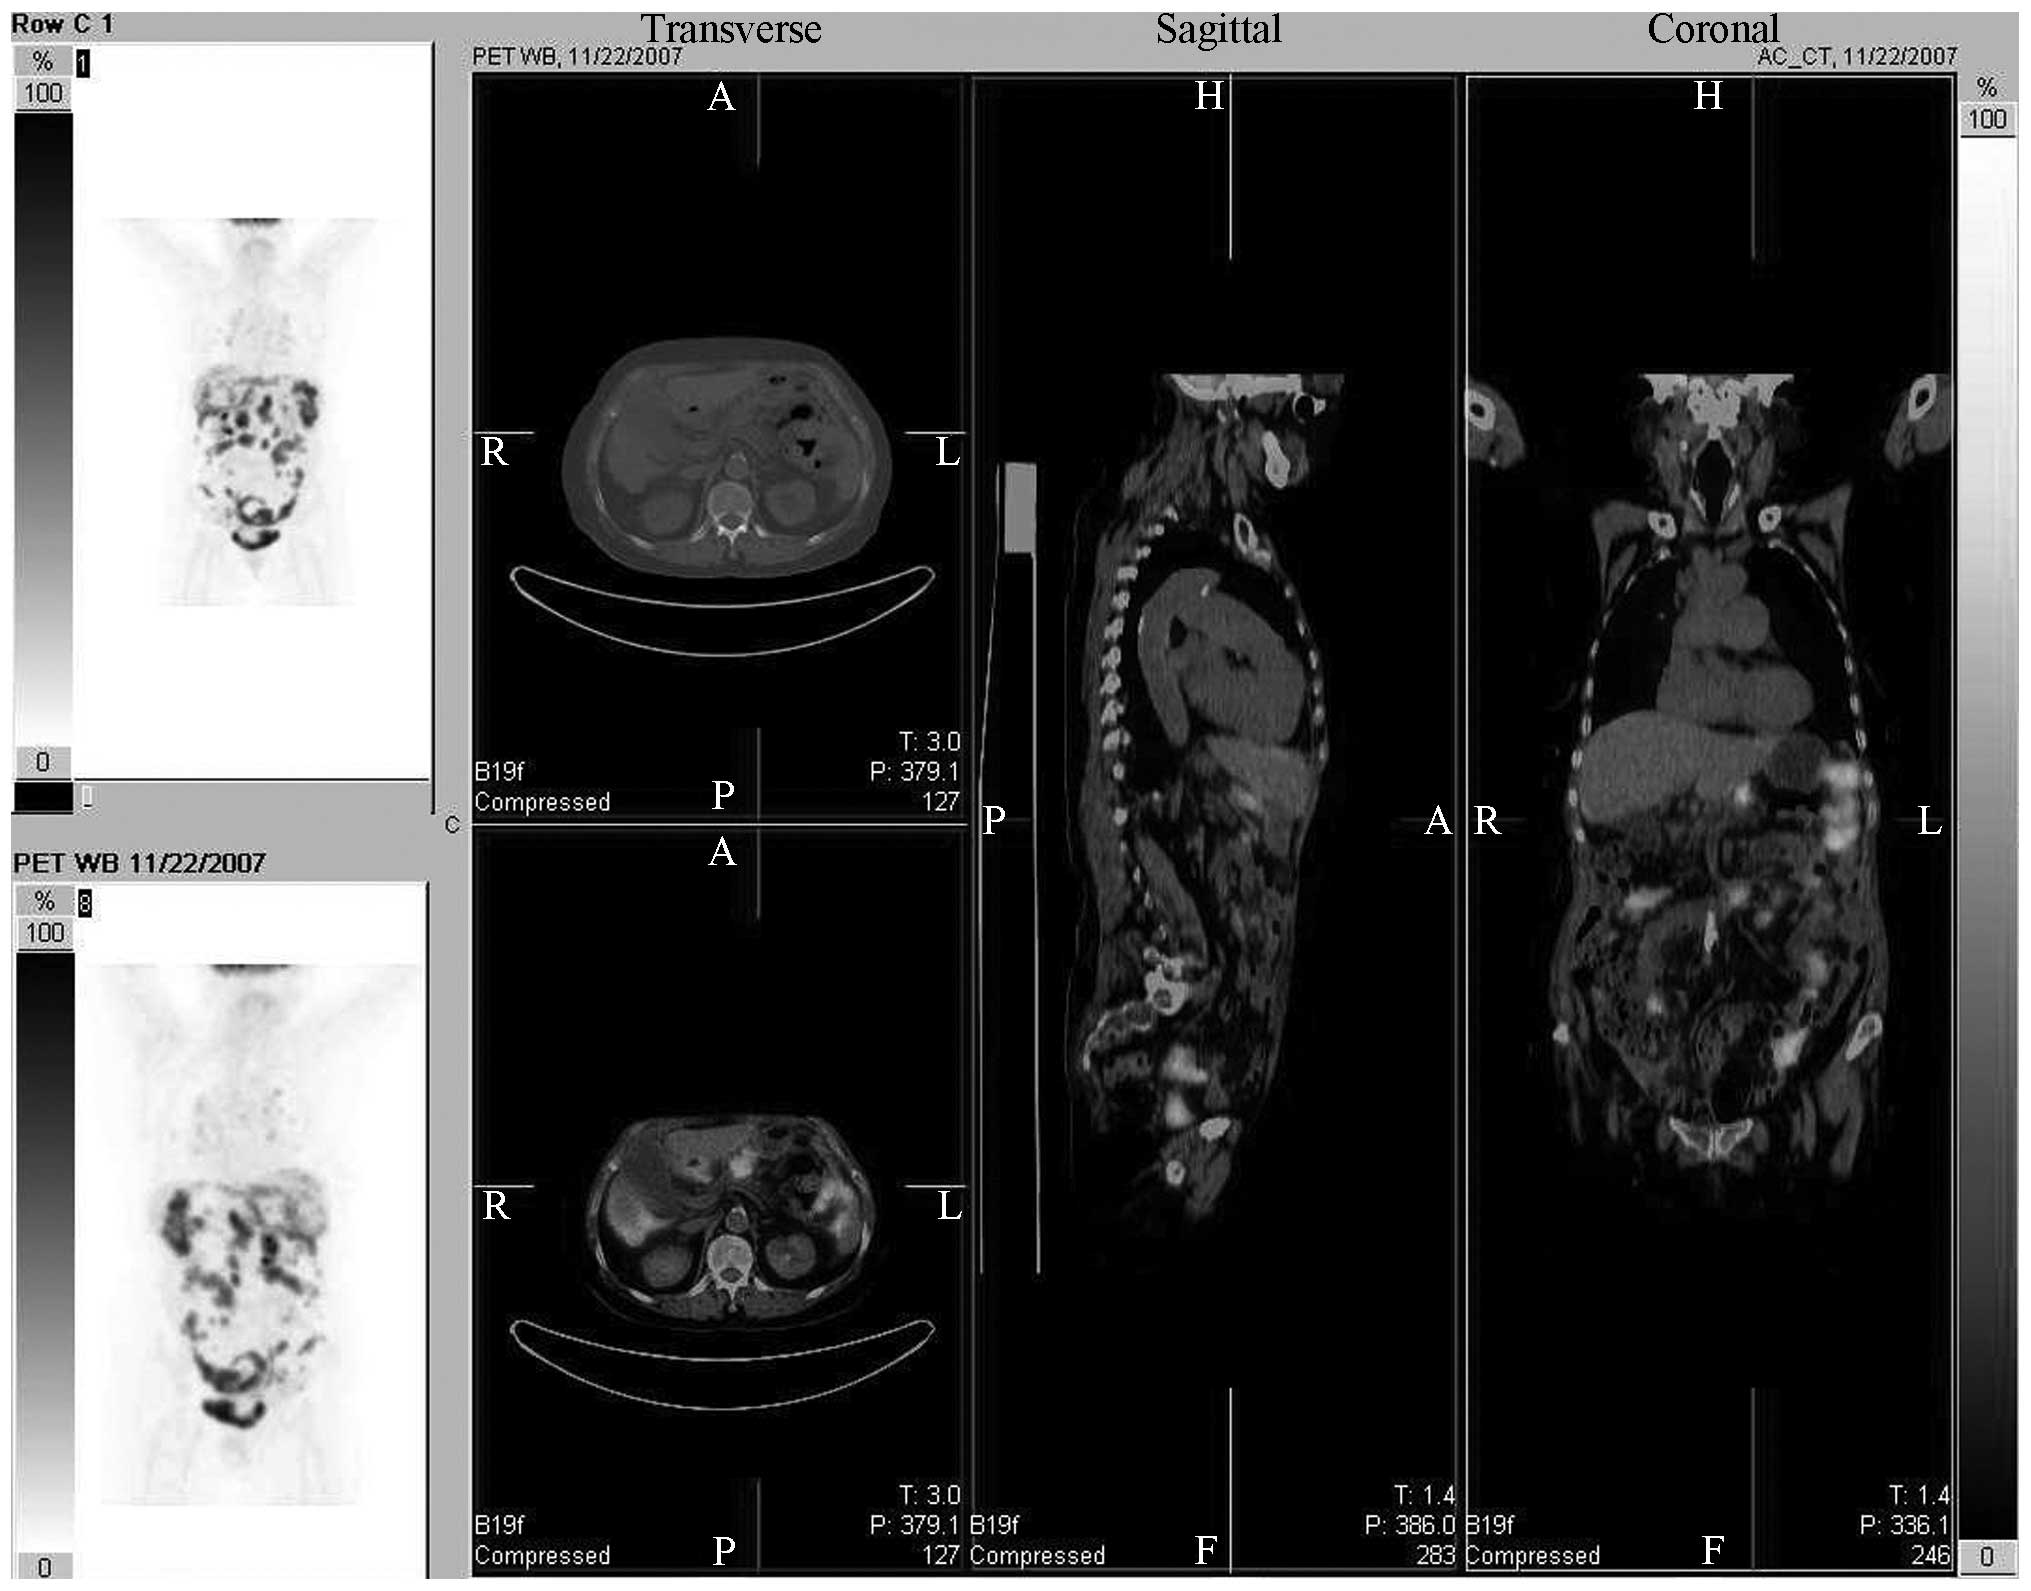

From June 1, 2007, a gradual improvement was observed in the patient’s condition. Dyspnea, abdominal distension and abdominal pain were significantly reduced, the patient had a significant improvement in appetite and urine and feces had returned to normal. The patient was upright and mobile. Bevacizumab was administered by IV infusion at a dosage of 400 mg every two weeks from June 9, followed by a dosage of 200 mg every two weeks from the end of November. On June 10, 2007, ultrasound showed that the massive left-side pleural effusion had disappeared. On June 29, 2007, a CT scan showed that the ascites, and the liver, spleen and pelvic lesions had disappeared. The patient’s CA-125 level was 31.17 U/ml on July 3, 2007, and 300 mg IP carboplatin was administered on November 4, 2007. Positron emission tomography-CT scans (Biograph™ TruePoint™ PET•CT; Siemens Medical Solutions USA, Inc., Knoxville, TN, USA) showed widespread metastases in the patient’s body on November 22, 2007 (Fig. 1). IP carboplatin was administered several times. The patient exhibited disease-free survival until July 2009 when disease progression was observed, followed by disease recurrence in August 2009. The patient died of multiple organ failure in September 2009.

Figure 1

Positron emission tomography and computed tomography scans showed widespread metastases in the body of the patient on November 22, 2007.